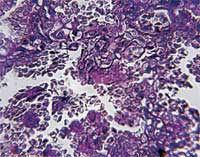

<p>In what may bolster humanity’s chances of winning over the smart and clever human immunodeficiency virus (HIV), researchers have discovered two powerful antibodies which may become an Achilles heel for the dreaded virus. Scientists will now try to exploit HIV’s newfound vulnerability to craft novel approaches to design a more potent AIDS vaccine. “The findings are exciting. We’ve got a new, potentially better target on HIV to focus our vaccine design efforts,” said Wayne Koff, senior vice president of research and development at the International AIDS Vaccine Initiative (IAVI). <br /><br />New bNAbs may help <br />The discovery of two broadly neutralising antibodies (bNAbs) may increase the chances of producing more such antibodies that in turn may reveal HIV’s additional vulnerabilities and give more vitality to the effort to develop an AIDS vaccine. Previous research conducted on primates showed neutralising antibodies prevented retrovirus infection in non-humans and can be a key for an effective HIV vaccine. Because HIV is a smart cookie that subtly changes its genetic make up when faced with survival threats, broadly neutralising antibodies are better suited to tackle the virus head on rather than those antibodies that can counter only specific HIV types. bNAbs are produced by a minority of HIV-infected individuals and distinct from other antibodies. Though conceptually it is better suited to protect against HIV, previous research with four similar antibodies did not yield much. <br /><br /> “The four previously identified bNAbs are the subject of intensive investigation. However, these targets have been less accessible to immunogen design (vaccine development) than what we hope will be the case for the two new antibodies (PG 9 and PG16) based on the breadth and potency of these bNAbs,” Koff told Deccan Herald. <br /><br />Why is the IAVI pinning such high hopes on these new candidates? “These new antibodies attach to a novel and potentially more accessible site on HIV,” said Dennis Burton, professor of immunology and microbial science at the Scripps Research Institute in La Jolla, California and scientific director of the IAVI. <br /><br /> The antibodies target a region of the virus’s surface protein required to infect cells. For invading a cell, the virus uses two glycol-proteins, termed gp120 and gp41, which have evolved to thwart immune attack. That’s why those four were proven difficult to exploit in designing a vaccine. On the contrary, PG9 and PG16 target regions of gp120, unable to change in the face of a vaccine attack. They expose the virus’ vulnerability and select themselves as better leads to develop a vaccine by offering “breadth of neutralisation.”<br /><br />Breadth of neutralisation is important because any effective AIDS vaccine must provide protection from a diverse range of prevalent types of HIV circulating globally. PG9 and PG16 are the first bNAbs to have been identified in more than a decade and are the first to have been isolated from donors in developing countries where the majority of new HIV infections occur. <br /><br />Reporting their findings in the journal Science, scientists from Scripps Research Institute, California and two biotech companies, Theraclone Sciences and Monogram Biosciences said that they looked for bNAbs rather than the regular ones because of the variable nature of the virus. <br /><br />The effort is distinguished by its emphasis on identifying antibodies that neutralize subtypes of HIV circulating primarily in developing countries. More than 1800 blood samples were collected from seven sub-Saharan countries and Thailand, Australia, the United Kingdom and the United States to find out these antibodies. <br /><br />Repository stocks of various HIV subtypes kept at different institutes were utilised for testing the efficacy of the bNAbs. They were also found effective against sub type C, the commonest HIV strain found in India. “The two new bNAbs have neutralised a wide spectrum of subtype C viruses, including some HIV isolates from India. So, yes they would be expected to neutralize a broad spectrum though not 100 per cent of isolates circulating in India,” Koff said. Two new technologies were used to identify the bNAbs. <br /><br /> One was a micro-neutralization assay developed by biotech company Monogram and the second one is a high-throughput process to carry out huge numbers of screening tests at the same time and get results faster. Another biotech firm Theraclone developed that. <br /><br />“If you think of it as a fishing expedition, we were previously using the wrong bait. We reasoned that the best approach to identifying antibodies with the most potent and broad neutralizing activity was to screen directly for their ability to block HIV infection. Our assay has opened up new avenues for exploration,” said Christos Petropoulos, chief scientific officer at Monogram Biosciences.</p>